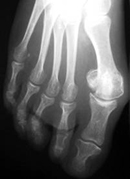

El hallux valgus, popularmente conocido como juanete, es una deformidad del dedo gordo del pie. Esta deformidad altera el funcionamiento normal del pie y puede producir dolor. Se produce con mayor frecuencia en mujeres.

Hay diversos tipos de cirugía para tratar el hallux valgus. Dependerá del especialista y sus preferencias y formación. El hallux valgus puede operarse con cirugía percutánea o con cirugía abierta. Tanto una como otra, tienen sus ventajas e inconvenientes.

La cirugía percutánea, popularmente conocida como "cirugía con láser", se realiza mediante pequeñas incisiones con poco daño de las partes blandas. Nosotros aconsejamos cirugía percutánea para deformidades leves o moderadas.